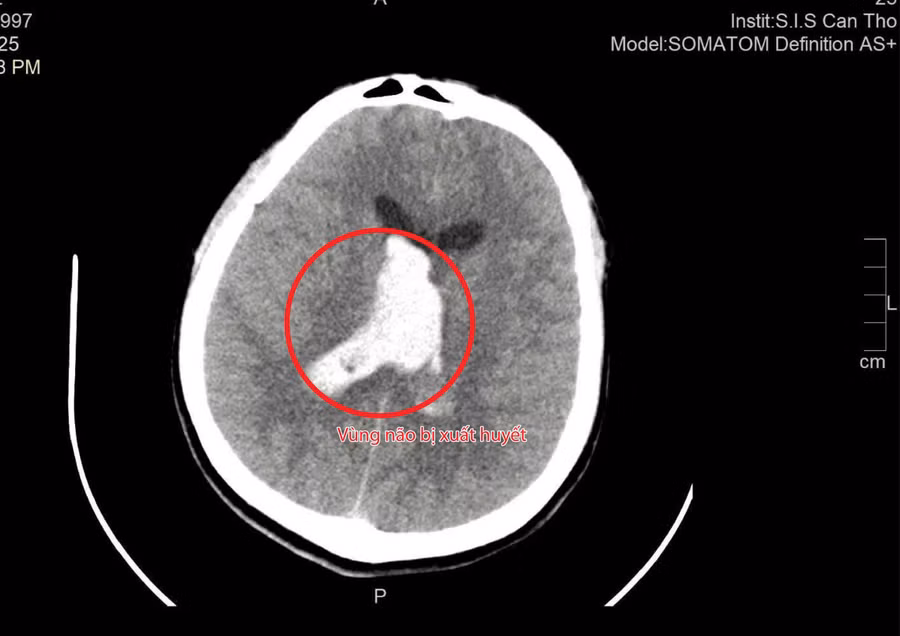

BS Tôn Nữ Thị Điểm, Khoa Ngoại tổng hợp của Bệnh viện chia sẻ, sau khi chụp CT não, các bác sĩ phát hiện bệnh nhân bị xuất huyết trong não và não thất, kèm phù não nặng. Nếu không được phẫu thuật kịp thời, áp lực nội sọ sẽ tăng nhanh, có thể đe dọa tính mạng (chỉ còn khoảng 20% cơ hội sống).

Hình ảnh vùng não bị xuất huyết. Ảnh: BVCC.